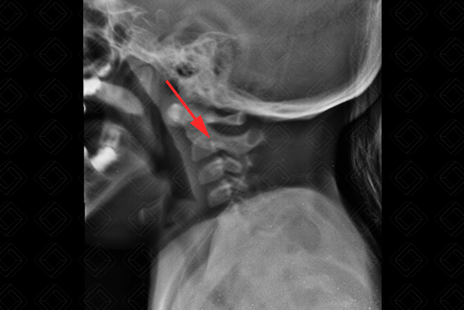

Texto alternativo para a imagem Figura 2. Créditos: Dra. Elazir Mota - Rio de Janeiro/RJ

Descrição das figuras 1 e 2: Radiografia cervical. Presença de osso omovertebral à esquerda (setas vermelhas). Diante deste achado na criança, com deformidade da cintura escapular, sempre buscar pela possibilidade de síndrome de Sprengel.

• Radiografia de coluna cervical: A avaliação inicial comumente é realizada por meio de radiografia de coluna que, na maioria dos casos, detecta com facilidade o osso omovertebral (imagens acima);